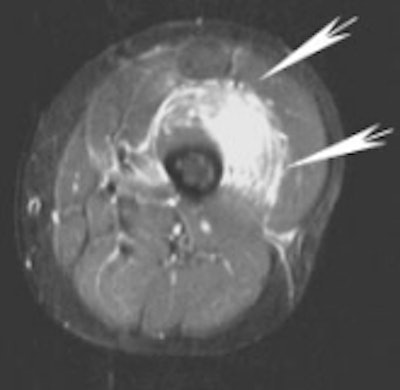

| Same patient, axial MRI, FSE T2FS. Arrows point to the hematoma in the vastus intermedius. |

The protocol for the MR scan included images in the axial plane, T2-weighting, fast spin echo (FSE), and fat saturation. As with the ultrasound, focal fluid collections were surrounded by diffuse muscle edema.